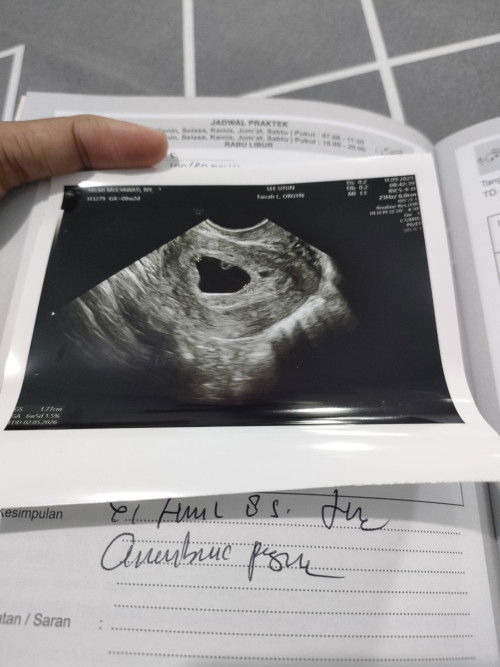

PCOS atau tidak‼️

Bunda apakah gambar usg transV ku itu terdapat PCOS? 😭 Dokterku tidak menjelaskannya, tpi aku lihat² kek ada bulet² di sebelah kanan🙏🏻🙏🏻🙏🏻

bunda pcos itu syndrom yang ditandai sel telur kecil dan tidak matang. ini USG nya berapa hari setelah mens? kalo aku USG tv buat cek telur tuh 2 Minggu setelah haid. kalo telurnya kecil2 dan tidak ada yg matang baru dibilang pcos. kalo diliat dari gambarnya itu kayak kantong hamil dengan yolksac. tapi gatau juga Deng aku bukan dokter soalnya. lain kali kalo USG tanyain aja, sayang loh udah bayar tapi gak dpt info.

Baca lagijangan overthinking dulu bunda. coba kontrol rutin kehamilan berikutnya ditanyakan ke doktrrnya, di rahim saya ada masalah ga ya dok. misalnya bunda kurang yakin bisa ganti dokter nya, kalo jawabannya baik baik aja, brarti bunda yg jgn overthinking. tetap tenang dan berdoa semoga bunda dan janinnya sehat terus

untuk perbandingan, ini contoh usg PCOS aku jadi bun sel telurnya terlihat kecil-kecil dan banyak, tidak ada yang matang padahal masa subur. bisa dicek lebih jelas lewat usg transvaginal. biasanya kalau usg perut gak terlalu nampak. semoga membantu yaa 🫶🏻

kayanya kemarin bunda sempet posting jg deh, tpi pertanyaan nya hasil usg kehamilan kosong atau tidak, bukan pcos..